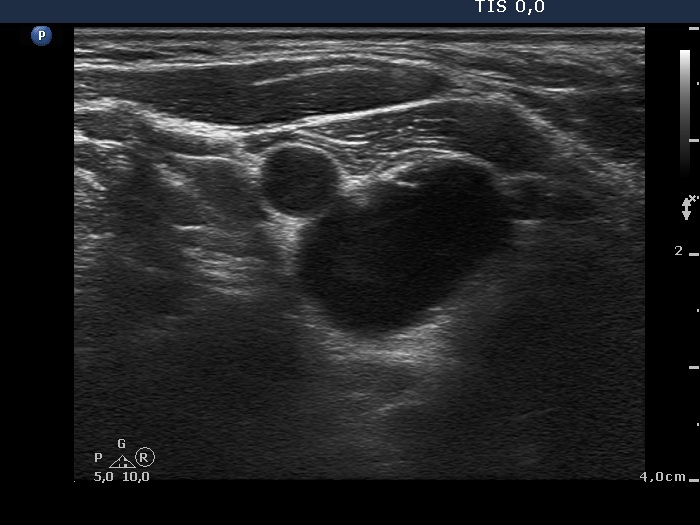

Ultrasonography: The thyroid was minimally-moderately hypoechogenic and presented fibrosis. There was a cystic lesion in the lower dorsal part of the right thyroid bed.

Twelve mL cystic fluid was aspirated. There were no cells on the smear.

Further laboratory tests aTPO 308 U/mL, calcium 2.25 mM/L, phosphorus 1.11 mM/L, parathormone 40.9 pg/mL (normal range: 10-65). The parathormone content of the cystic fluid was 383 pg/mL.